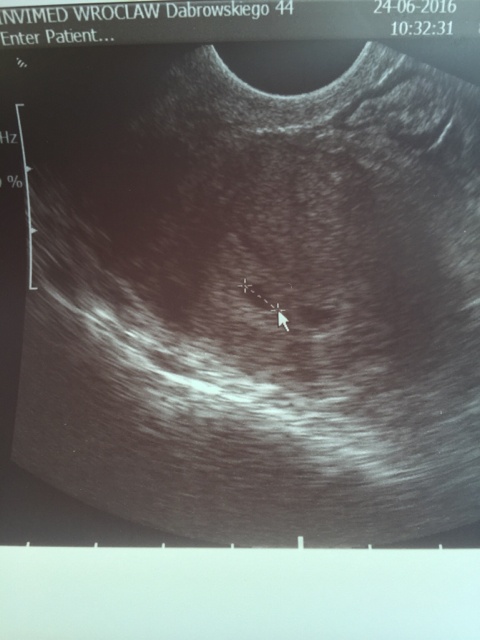

Nie ogarniam Was dziewczyny, za rzadko wchodzę chyba [emoji6] ale dziś nie mogę się nie pochwalić. Jestem w ostatnim dniu 5 tygodnia, dziś byliśmy na usg potwierdzającym ciąże (tak szybko bo moja ginka jutro na urlop wyjeżdża) . Co prawda serduszka żadnego nie zobaczyłam za to były 2 RÓWNIUTKIE PĘCHERZYKI 7-milimetrowe !!! Bedą BLIŹNIĘTA [emoji3] za tydzień kolejne usg.

1466782454-yw2osx.jpeg